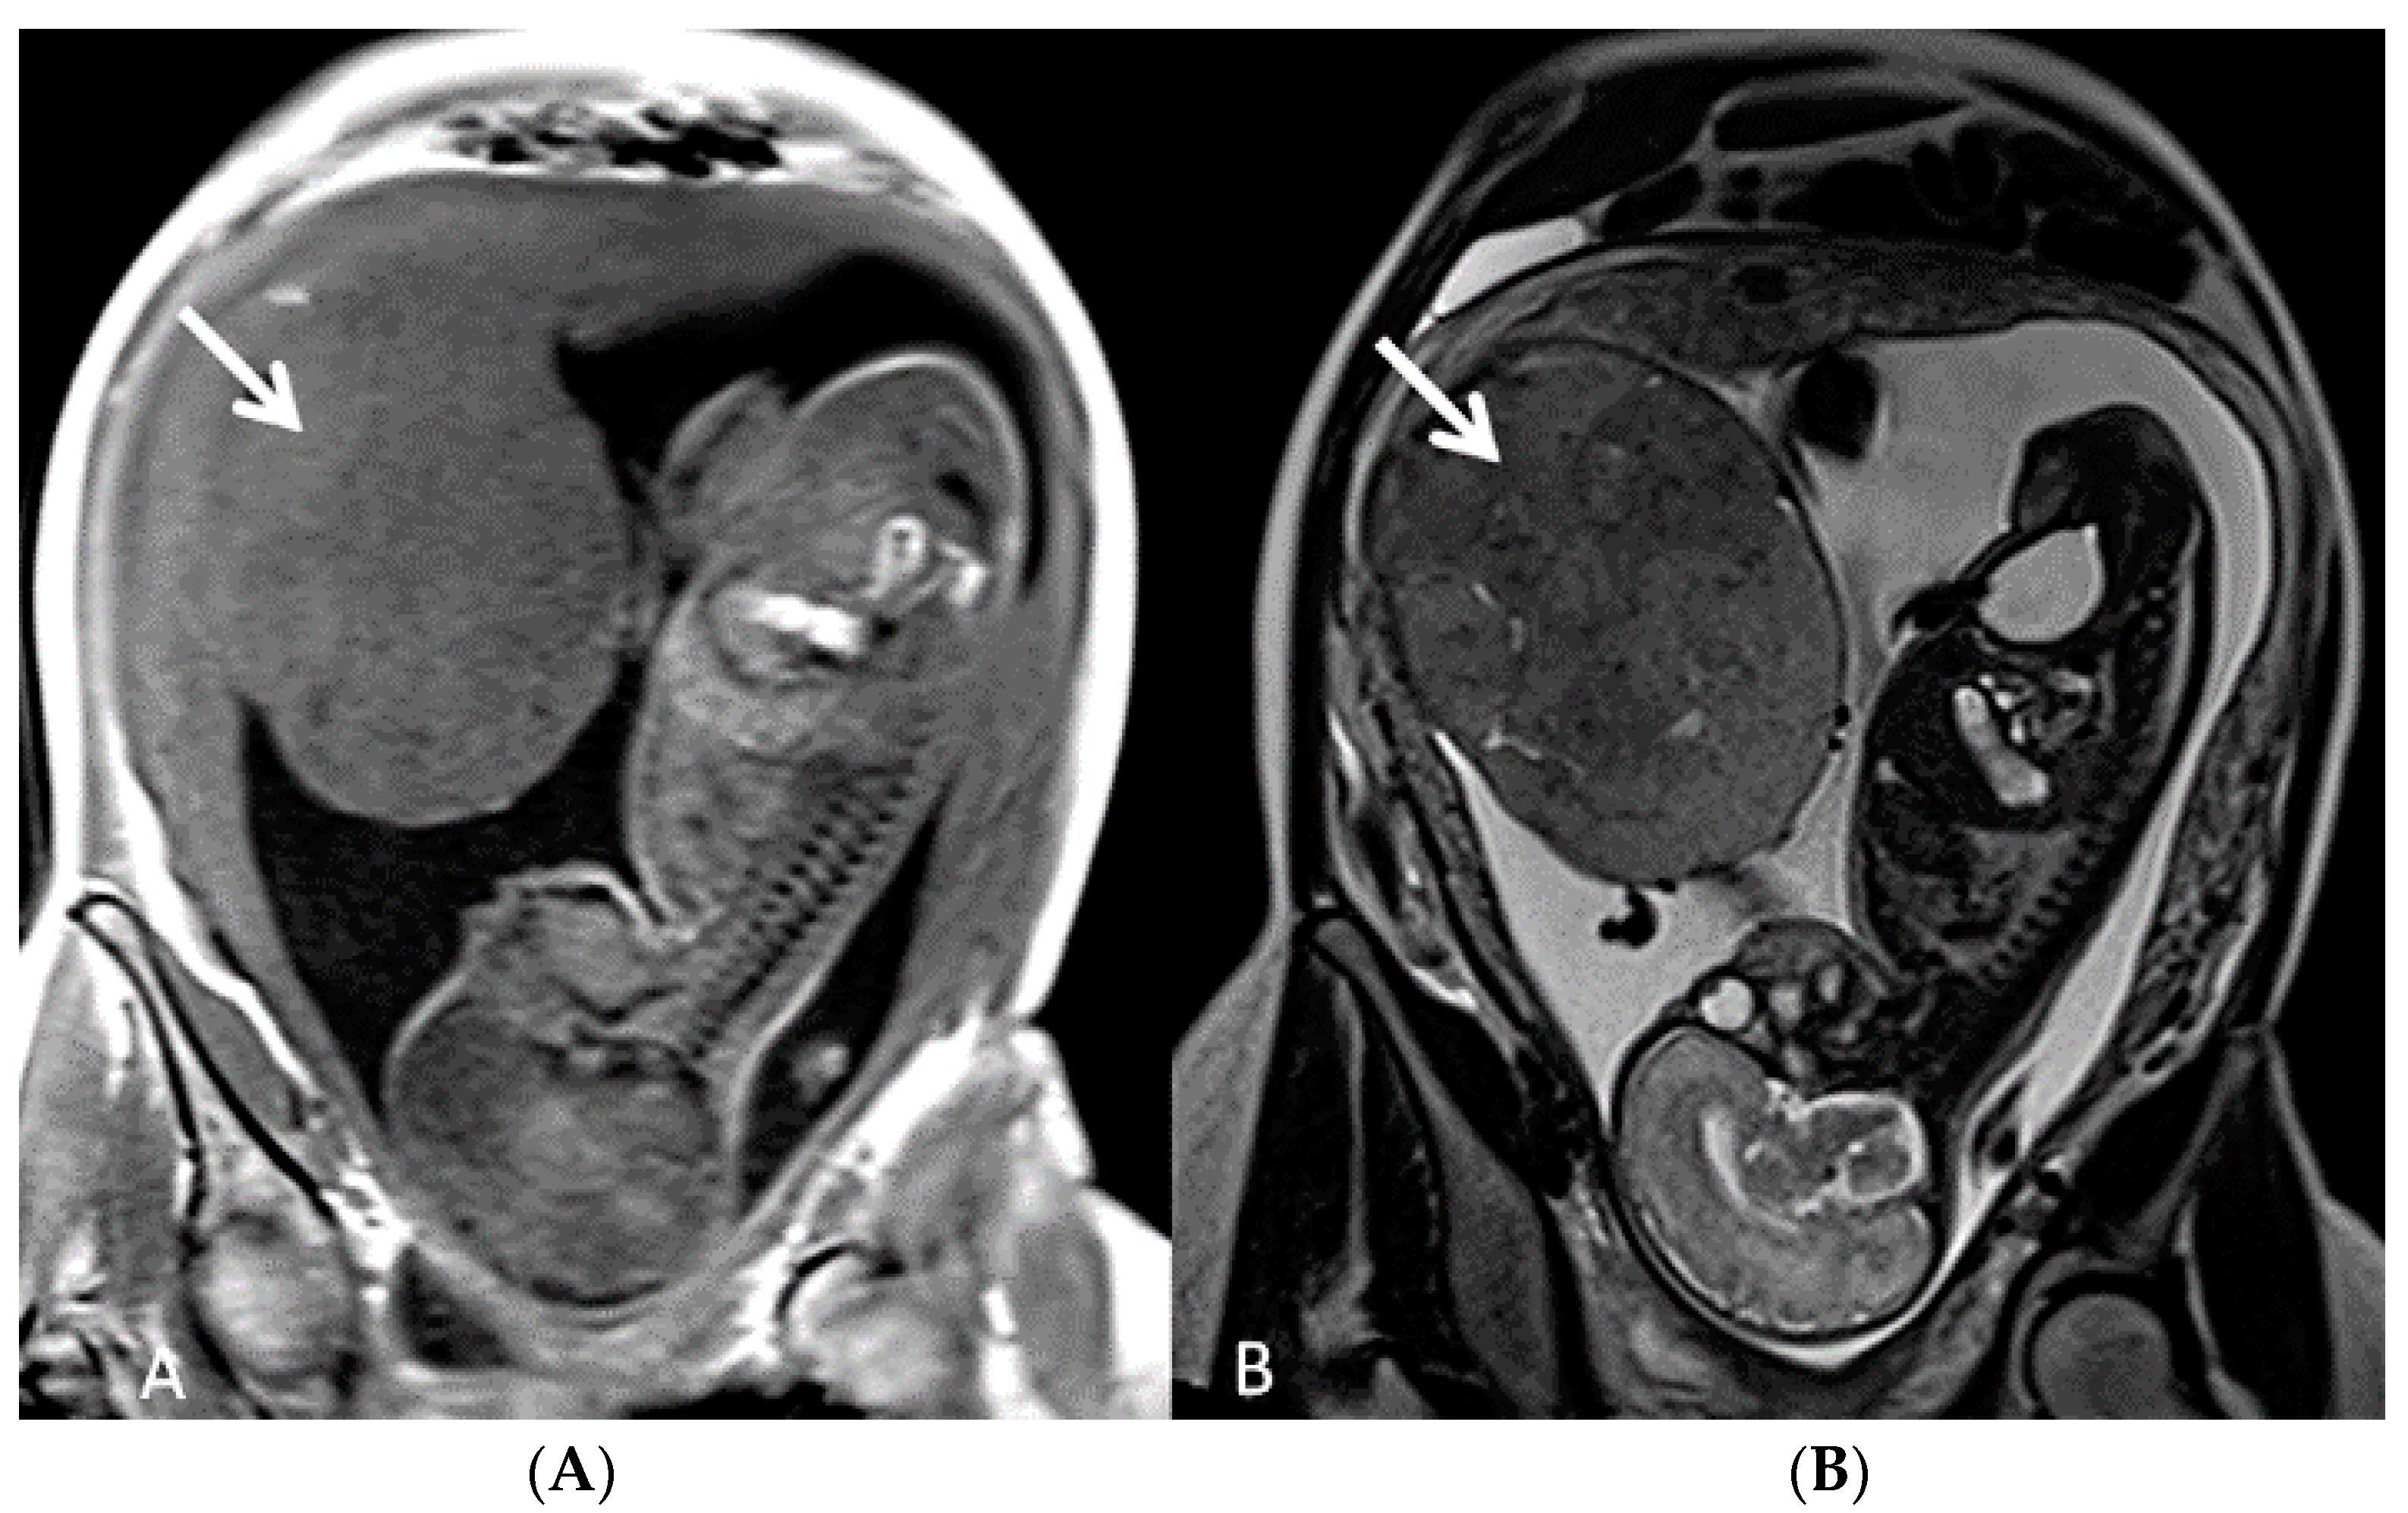

Placenta praevia is a condition in which the placenta develops within the lower uterine segment and overlies the cervix [7]. Previous terminology, such as symmetric or complete, has now been replaced and the condition is now classified as placenta praevia major [7,21,22] On the other hand, if the placenta does not overlie the cervix, but its edge is located within 2.0 cm of the cervical os, it is called a low-lying placenta. This type of placenta is now defined as placenta praevia minor [7,22]. The incidence of placenta praevia is seen in around 4 to 5 of 1,000 pregnancies, and the risk factors associated with this condition are advanced maternal age, multiparity, previous placenta praevia, chronic hypertension, diabetes mellitus, smoking during pregnancy, multiple gestation and assisted reproductive technology (ART) [22]. This placental anomaly, besides being one of the major risk factors for PAS, is associated with maternal bleeding, Cesarean section and prematurity [7,22,23]. The use of transvaginal ultrasound allows for the better definition of the placental anatomy in relation to the cervix with a sensitivity of 88% and specificity of 99% [22]. In the face of placenta praevia and low-lying placenta, the gray-scale third trimester ultrasound has a great negative predictive value in detecting cases of accretism when normal hypoechogenic space is seen between the uterus and placenta and through the lack of the visualization of placental lacunae [24]. Ultrasound has shown a low sensitivity in the diagnosis of PAS in mothers with posterior placenta praevia while MRI has superior accuracy and fewer false negative results, but higher accuracy was obtained through a combination of both techniques [23,25,26] (Figure 3 and Figure 4).

Figure 4.

Fetal MRI (sagittal T2) performed at 30 weeks and 26 week’s gestation in two different fetuses (A,B), demonstrating a placenta praevia major and accretism. (Legend: Pl: placenta; Cx: cervix).